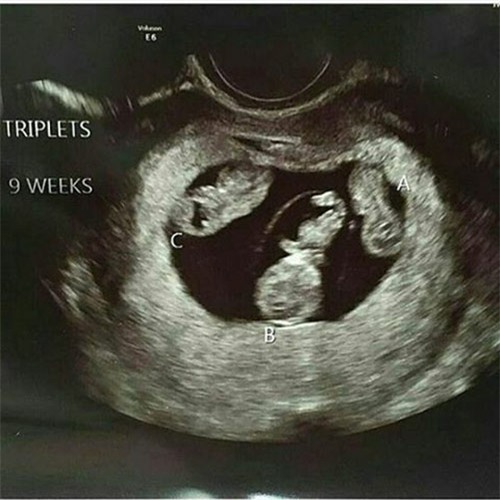

Mới đây, bức ảnh siêu âm 3 thai tuyệt đẹp được bác sĩ Vũ Quang chia sẻ trên mạng xã hội đã thu hút sự chú ý của cư dân mạng với hơn 1,1 nghìn lượt người yêu thích và hàng chục bình luận bày tỏ tình cảm yêu mến, thích thú, thậm chí còn người còn nhờ bác sĩ tư vấn cách để được mang thai đôi, thai ba giống như trường hợp trong hình.

Bức ảnh siêu âm tam thai của bác sĩ Vũ Quang nhận được hơn 1,1 nghìn lượt yêu thích.

Bức ảnh này tôi siêu âm trong một lần khám thai cho bệnh nhân bị đau bụng theo dõi dọa sảy. Bệnh nhân có hoàn cảnh khó khăn về mặt con cái. Hai vợ chồng điều trị vô sinh đã được 9 năm, tâm lý rất nặng nề chuyện con cái. Người vợ năm nay 35 tuổi nhưng bây giờ mới lần đầu mang thai.

Lần này thai phụ có 3 thai ở tuần thai thứ 9 nhờ phương pháp thu tinh ống nghiệm (IVF). Hai ngày trước bệnh nhân cảm thấy tức bụng dưới nhiều vì nhà cũng xa Hà Nội và ngại đi khám nên cũng chủ quan đến khi có ra ít máu âm đạo mới đi khám. Sau khi thăm khám tôi cũng được biết bệnh nhân đã được hẹn đến ngày giảm thiểu phôi vì hạn chế việc sinh 3 do phải gặp nhiều nguy cơ thai sản.